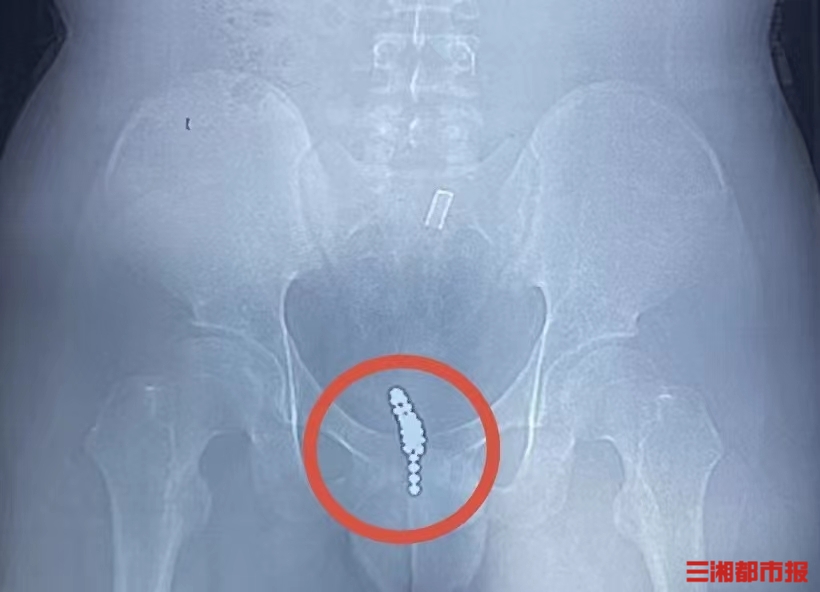

家人立即将他送往附近医院,通过泌尿系CT检查发现,膀胱内有一团串珠样异物。医生表示,由于磁力珠数量多、磁力极大,无法经尿道取出,将膀胱切开才能将异物取尽。

接下来的手术就像“夹娃娃”,由于磁力珠质地坚硬、吸附力超强,眼看就要夹出来却又掉了下去……最终,医生凭借精湛的手术技艺和超乎寻常的耐心,采用取石网篮、异物钳等手术器械“轮番上阵”,成功将25颗磁力珠“一网打尽”,避免了创伤较大的开放手术。术后复查X线显示,异物被完全取尽,患者目前已康复出院。